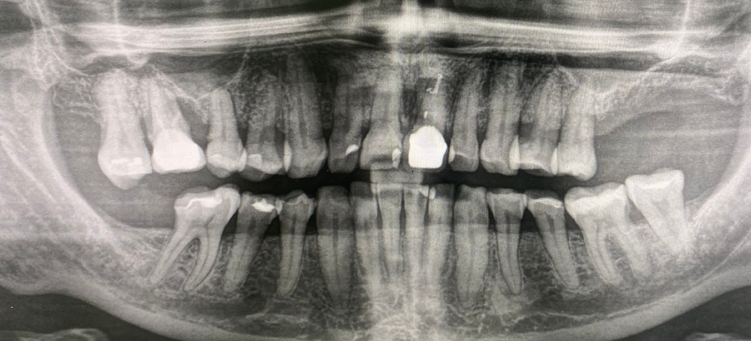

Установка имплантатов Straumann BLT